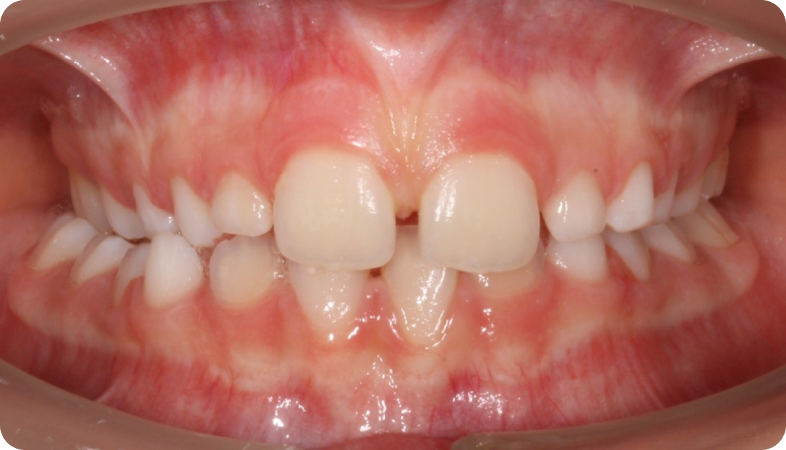

Cas cliniques